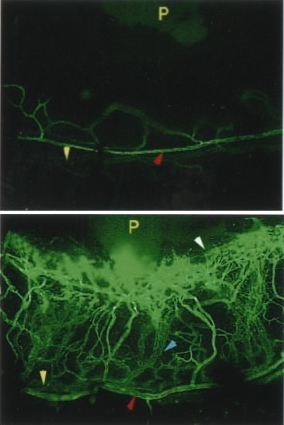

SN-induced angiogenesis

in the limbus vein

(upper panel = control).